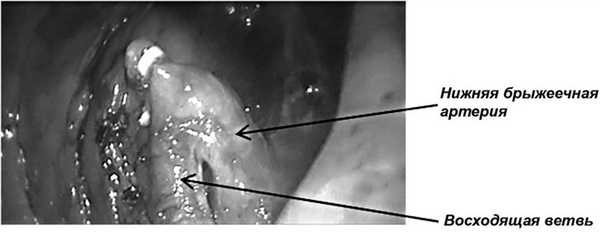

В левой подвздошной области разрезом до 5-6 см выполняем лапаротомию и устанавливаем порт «Нandportsystem» (рис. 3, 5). Операционный стол переводится в положение Тренделенбурга (положение больного с опущенным головным концом и приподнятым тазовым) с наклоном вправо (рис. 4). Четкий контроль над опасными анатомическими структурами делает этот этап операции достаточно быстрым. При мануально-ассистированной технике устье нижней брыжеечной артерии и ее восходящая ветвь становятся основными ориентирами границы выполнения лимфодиссекции (рис. 5 и 6).

Рис. 7. Пересеченная нижняя брыжеечная артерия выше отхождения ее восходящей ветви.